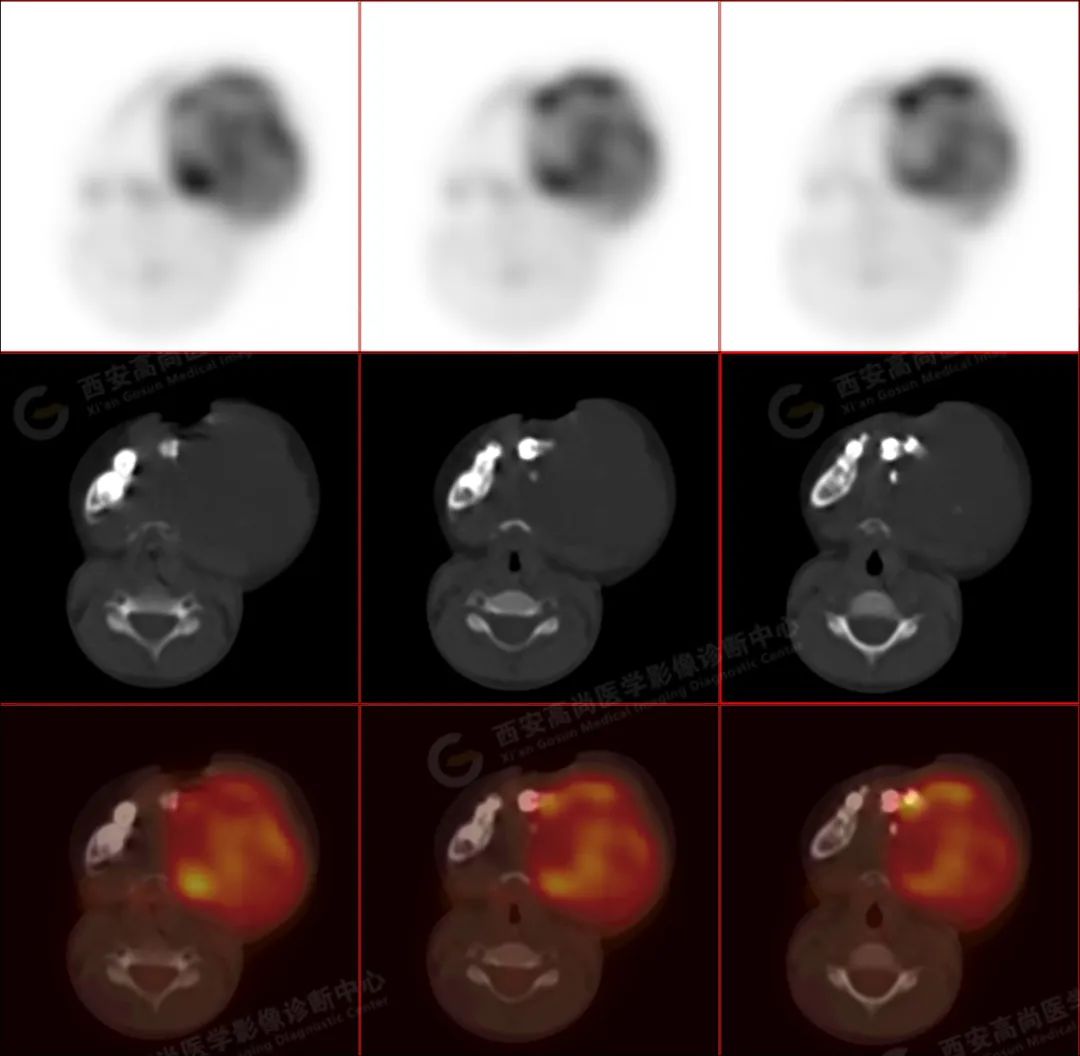

左侧下颌区可见巨大团块状软组织肿块,大小约 6.6 cm×5.8 cm×6.1 cm,向上达左侧颞下窝上缘,向下达下颌前联合,相邻左侧咬肌、颊肌等肌肉组织分界不清楚,左侧口底、咽部、腮腺受压改变,肿瘤包绕及侵犯左侧上颌升支、蝶骨翼突外板,呈 FDG 代谢不均匀异常增高,考虑为恶性病变,横纹肌肉瘤可能性大。

3.PET/CT 能够提供肿瘤代谢信息,并且提供肿瘤分期。分化程度越差的病灶 FDG 代谢明显增高。